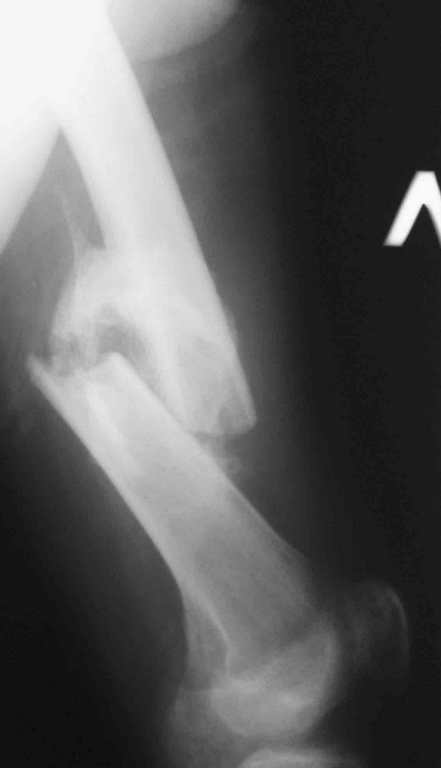

[Ortho] 32- летний пациент с переломами обоих бедер после неудачного оперативного и консервативного лечения.

Имя     : Fem L 2.jpg